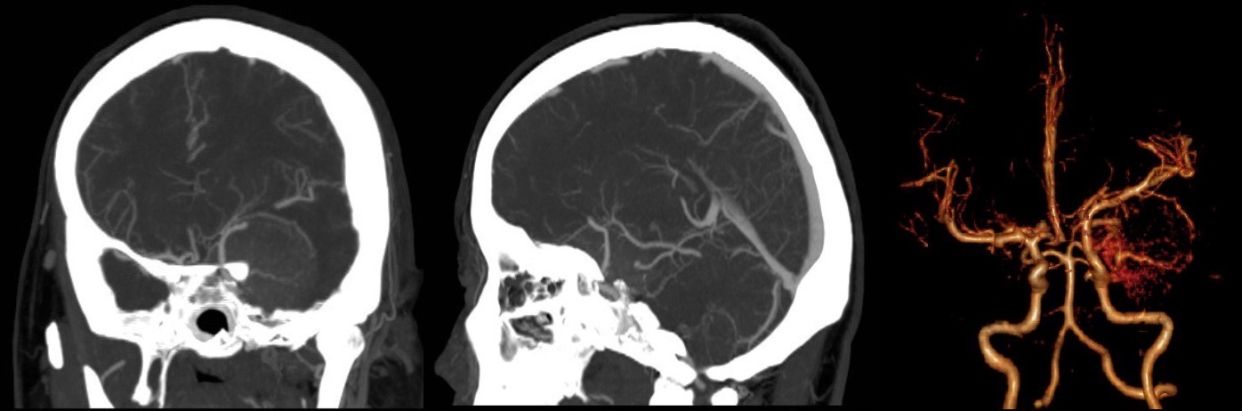

CTA检查:可见颈外动脉分支参与供血,颈内动脉颅内段及大脑中动脉分支受压移位。

CTA血管造影及三维重建: